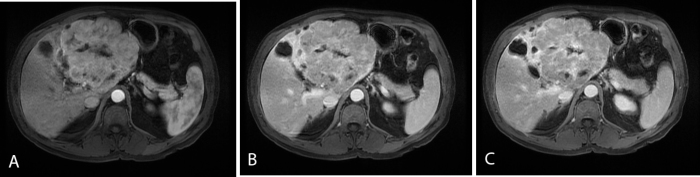

Figure 5.

65-year-old male with pancreatic differentiated MANEC within the left hepatic lobe. Contrast-enhanced axial LAVA FS images during the arterial phase (A), at 5 min (B), and at 10 min (C) demonstrate arterial enhancement of the MANEC followed by slight washout relative to the liver. The central scar demonstrates delayed enhancement (C).